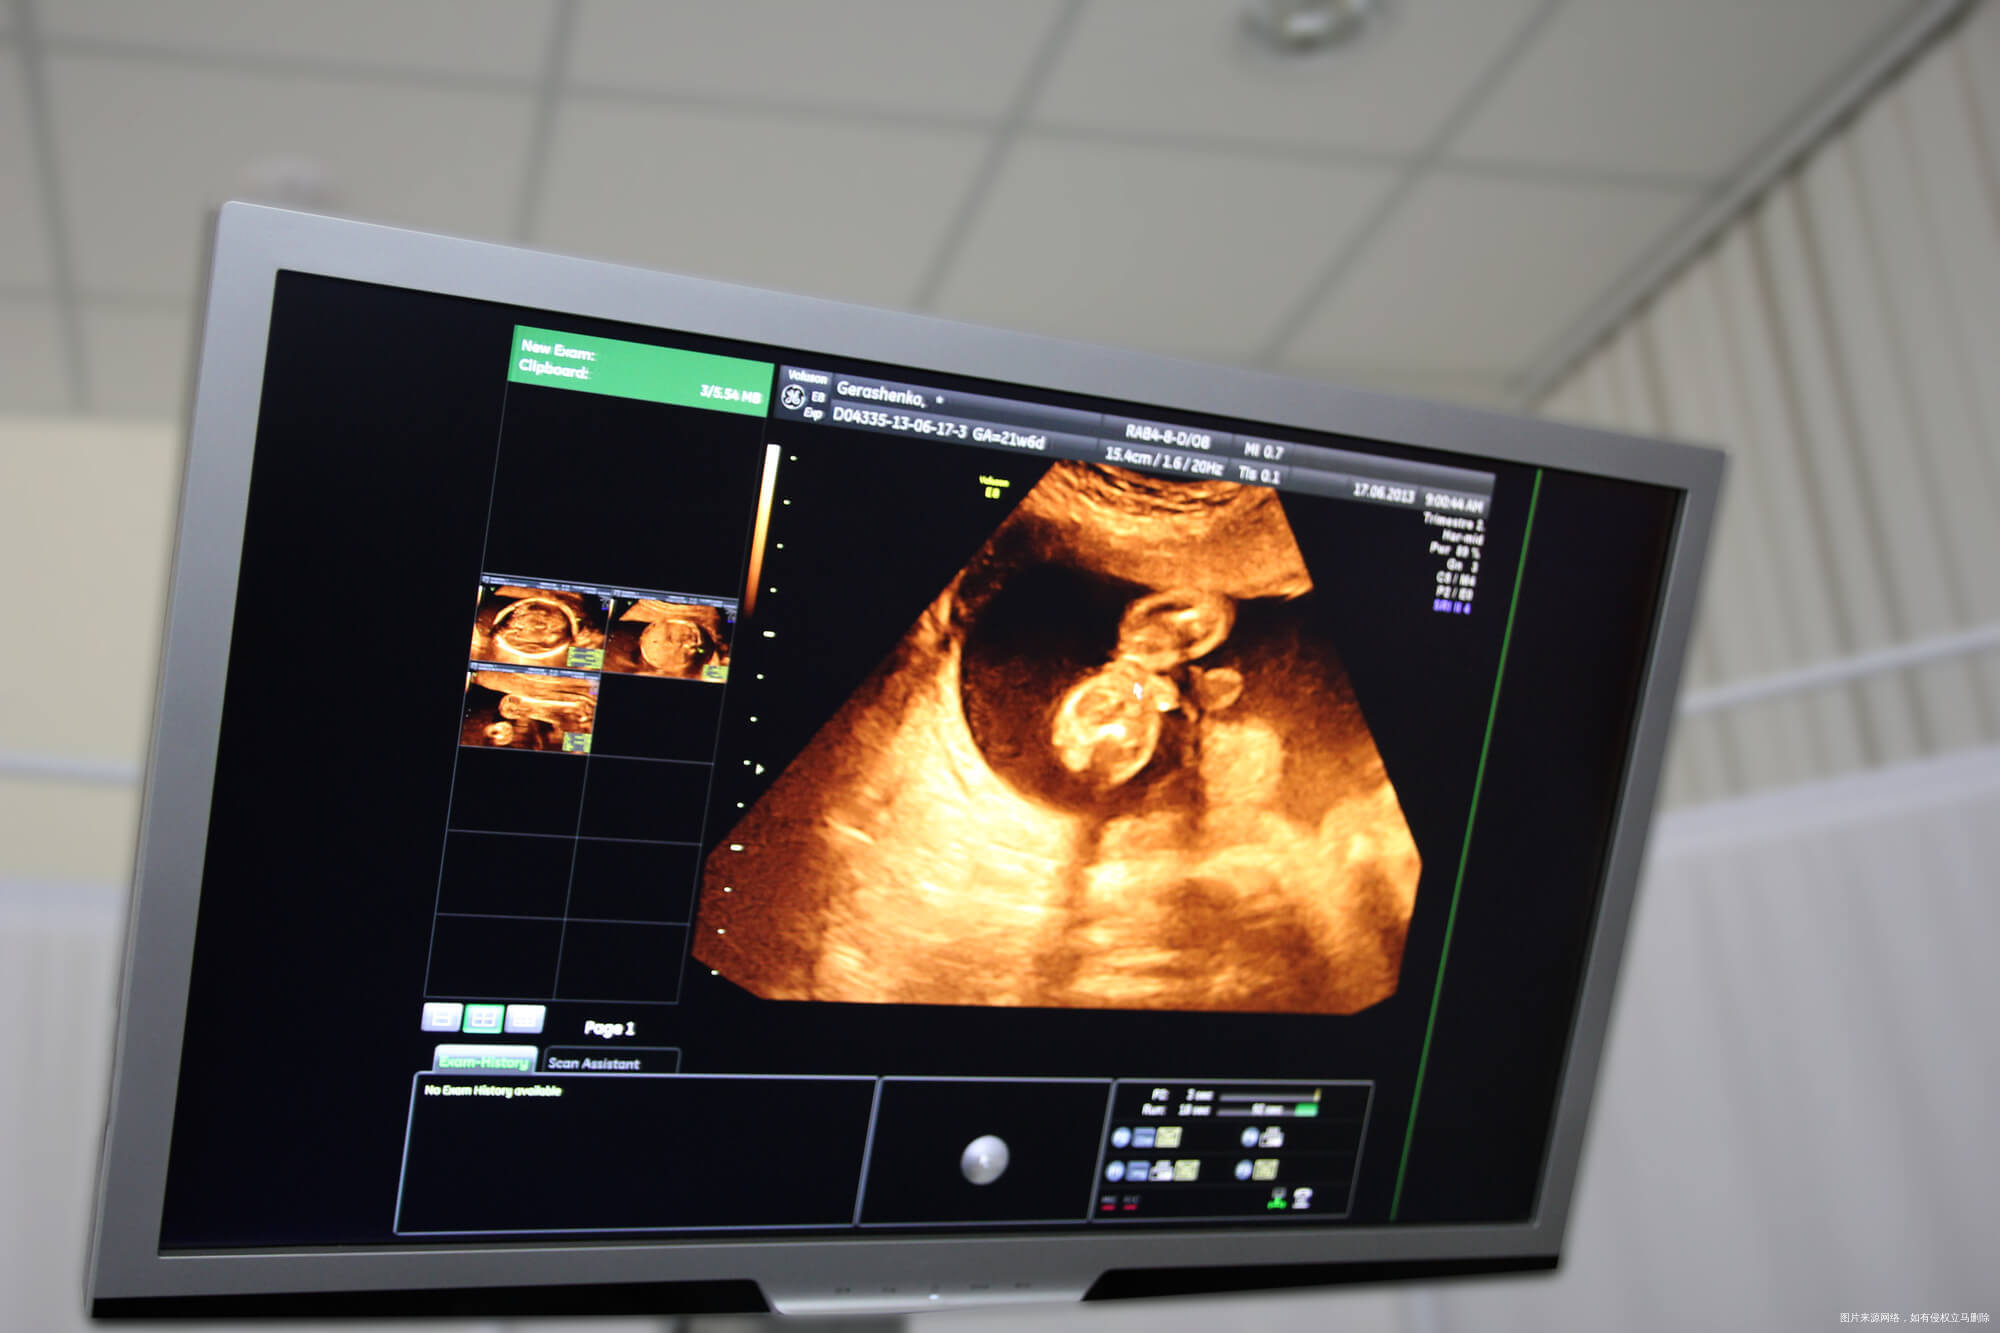

近几年,不孕不育人群并没有减少,反而在增加,主要是由于现在生育年龄普遍增大、过早进行人工流产、饮食环境差、不良生活习惯、先天性疾病等。多种多样的不孕也加大了治疗难度,一些夫妻经过了多年的治疗依然不能怀孕,这样的情况下可以考虑做试管婴儿的,对于试管婴儿很多人通过科普资料已经有了一些了解,但是对于细节了解还是很少,最近有患者提出这样的问题:试管婴儿是冷冻卵子还是受精卵呢?必须冷冻吗?今天就这个疑问我们来做个简单的介绍。

卵细胞冰冻指把收集到的卵细胞放进-196℃的液态氮中保存,待合适可能性将卵细胞解除冻结,经体外受孕后做到生孕目的性。按惯例,提议冰冻的卵细胞储存5年,三十五岁以前冷冻卵子,随年纪增加卵细胞品质可减少,染色体变异可能性比较大,储放太久,解除冻结时孕妈年纪比较大也可减少怀孕可能性。卵细胞在液态氮中基础代谢、分子运动是终止的,技术性扎实冰冻時间不受到限制,考虑到孕妈年纪状况,提议尽可能减少冰冻時间。

已经结婚女士通常在两类状况下,具有资质证书的医院门诊才会为其冷冻卵子。一种是不孕症女士在试管婴儿取卵当天,老公不可以立即提供精液,另外拒绝供精做试管的;第二类是身患肿瘤的女士,在对全身性开展比较大使用量放疗化疗前,能够 将卵细胞拿出来冰冻,储存有着子孙后代的可能性。鉴于现阶段全世界仅有一百多个冰冻卵婴儿,年纪都不到10岁,将来会否受到冷冻卵子的危害尚欠缺长期观查,所以这一技术性都还没获得彻底认证。由此可见,冷冻卵子是备不时之需,平常人或是不必随意来尝试。

试管婴儿是冷冻卵子还是受精卵就为大家介绍这些,通过上面的介绍,大家得知冷冻的是哪一部分还是看自己的选择,是有哪些需求,医生也会根据大家的想法提出相应的意见。如果想通过试管婴儿治疗怀孕,在此之前是需要做很多检查的,如果身体情况不允许是不能接受试管婴儿的,这些都是身体情况决定的,如果身体条件不适合医生也不会同意接受手术治疗的。